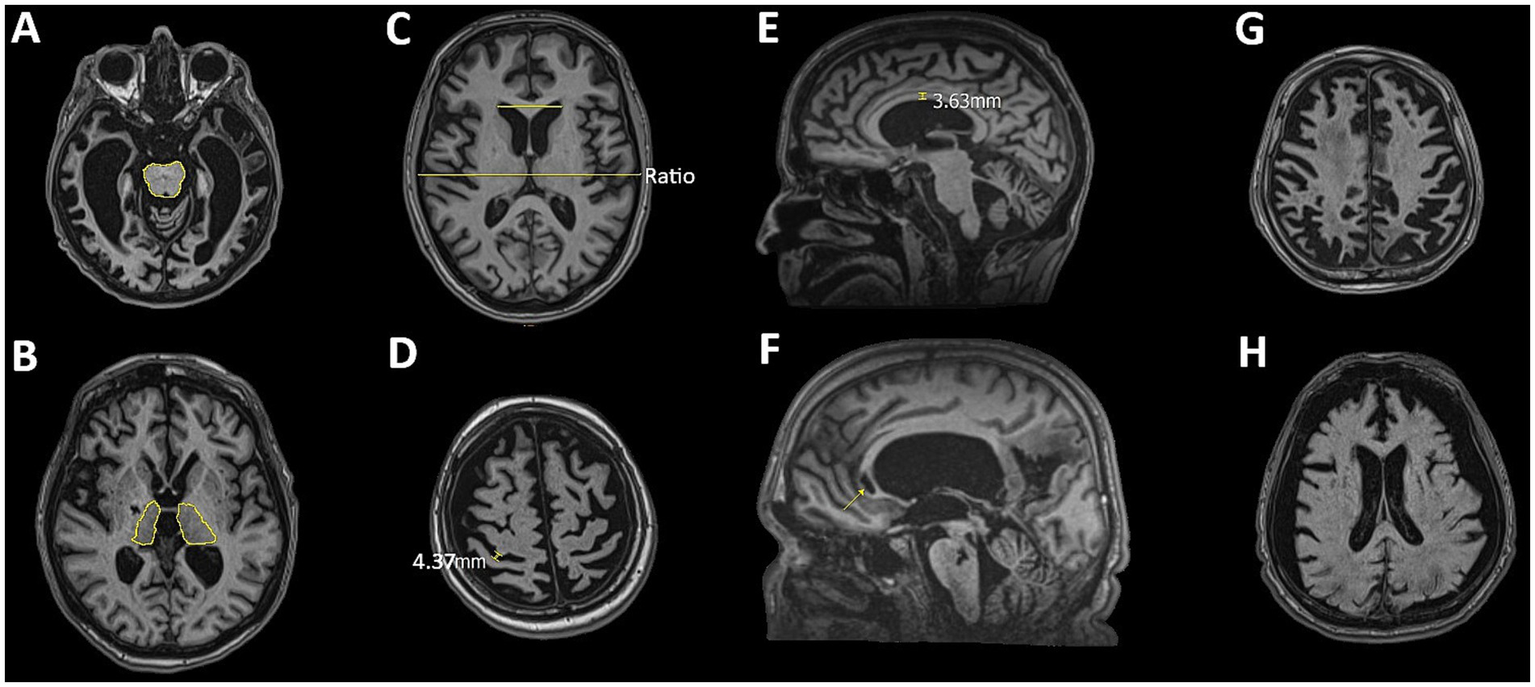

Figure 2

Representative MRI slices illustrating features assessed in the qualitative analysis: (A) brainstem atrophy, (B) thalamic atrophy, (C) ventricular enlargement assessed using the Evans Index, (D) sulcal widening, (E) corpus callosum thinning (degeneration), (F) corpus callosum lesions, (G) diffuse cortical atrophy, and (H) effacement of the gray-white matter border.

DCA, BS/T atrophy, and CC lesions were assessed categorically (presence/absence). VE was quantified using the Evans Index (EI), with moderate VE defined as EI = 0.31–0.74 and severe VE as EI > 0.74. SW was evaluated at the level of the central sulcus. Moderate enlargement was defined as subarachnoid space dilation ≤ 0.4 cm; values > 0.4 cm were classified as severe. Leukoaraiosis was graded based on the presence of periventricular caps, smooth rings, and confluent changes: moderate if limited to periventricular zones, and severe if extending into deep and subcortical white matter. CC atrophy was measured at the midsagittal plane. Thickness between 0.2–0.4 cm was classified as moderate atrophy; values < 0.2 cm were considered severe (18). The analysis also noted the effacement or blurring of the GM/WM border and multiple lesions in the BS and thalamus. Major lesions—including global ischemia, large porencephalic cavities, and extensive damage affecting ≥30% of lobar or basal ganglia volume—were used as exclusion criteria for quantitative analysis (32). BS and thalamic atrophy were evaluated at multiple anatomical levels to ensure comprehensive coverage (see Figures 1, 2).